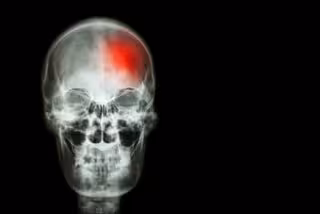

Nuevos factores de riesgo de la demencia tras un ictus

Ictus, cerebro, cerebrovascular

El mayor tamaño del hematoma y la ubicación son factores de riesgo asociados con la demencia tras una hemorragia intracerebral cuando un vaso sanguíneo en el cerebro se rompe, según explica un artículo publicado en la edición digital de 'Archives of Neurology'.

La hemorragia intracerebral (HIC) o ictus constituye un 15 por ciento de todos los accidentes cerebrovasculares y alrededor del 50 por ciento de la muerte y la incapacidad por ictus en todo el mundo. El deterioro cognitivo progresivo es frecuente después de la HIC, pero se sabe poco sobre sus factores de riesgo.